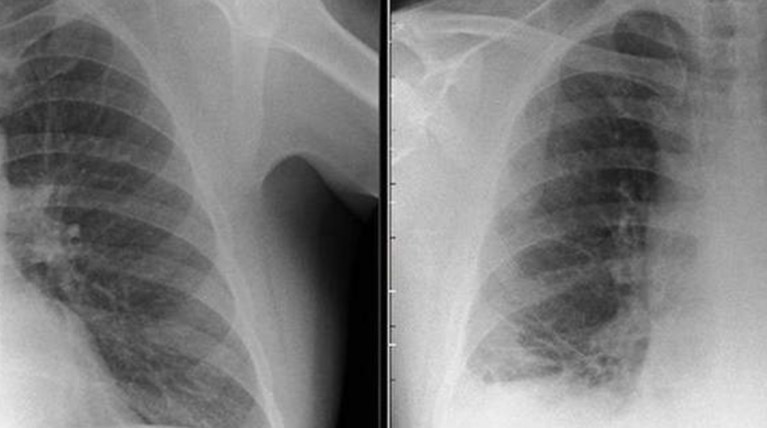

Οι γιατροί του Royal Preston Hospital στο Λάνκασιρ της βορειοδυτικής Αγγλίας έστειλαν άρον-άρον για εξετάσεις έναν ασθενή που υποπτεύονταν ότι είχε προσβληθεί από καρκίνο των πνευμόνων.

Φανταστείτε την έκπληξή τους όταν διαπίστωσαν ότι ο όγκος ήταν ένα μικρός πλαστικός κώνος Playmobil που είχε σφηνωθεί στον πνεύμονα του.

Ο 47χρονος είχε καταπιεί το παιχνίδι όταν ήταν παιδί. Του είχαν χαρίσει οι γονείς του ένα σετ Playmobil στα έβδομα γενέθλιά του. Το αξιοπερίεργο είναι ότι δεν είχε παρουσιάσει κανένα σύμπτωμα επί τέσσερις ολόκληρες δεκαετίες, μέχρι που άρχισε να βήχει δυνατά, να βγάζει φλέματα και να νιώθει έντονη αδιαθεσία.

Όπως ανέφερε το BMJ Case Reports οι γιατροί όταν είδαν τις ακτινογραφίες θεώρησαν ότι ο όγκος που διακρινόταν στον πνεύμονα του 47χρονου ήταν καρκίνος, μέχρι που έμαθαν την αλήθεια.